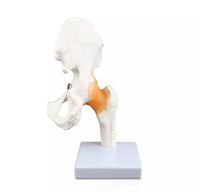

Modelo articulacion de cadera

El modelo puede mostrar la morfología estructural de la articulación de la cadera. Anatomía de la cadera y el fémur 1:1 tamaño normal y tiene una base.

Tamaño: 25x19x30CM

Tamaño: 25x19x30CM